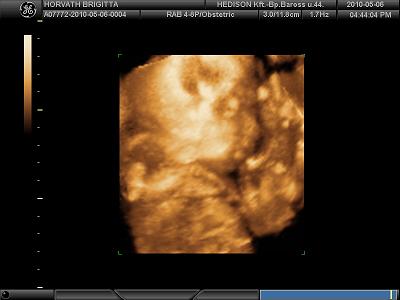

Vanilla, hát Monor tényleg itt van, sűrűn megyünk át vásárolni, meg upc-t fizetni:-)) Nagyon szép a babátok:-)) Jók lettek a 4d képek. Én eddig mindig a Barossba voltam, eddig mindig jó volt, kedvesek voltak nagyon. Az én kislányom szereti takarni az arcát nagyon nehéz őt lekapni:-)) Szégyenlős :-))